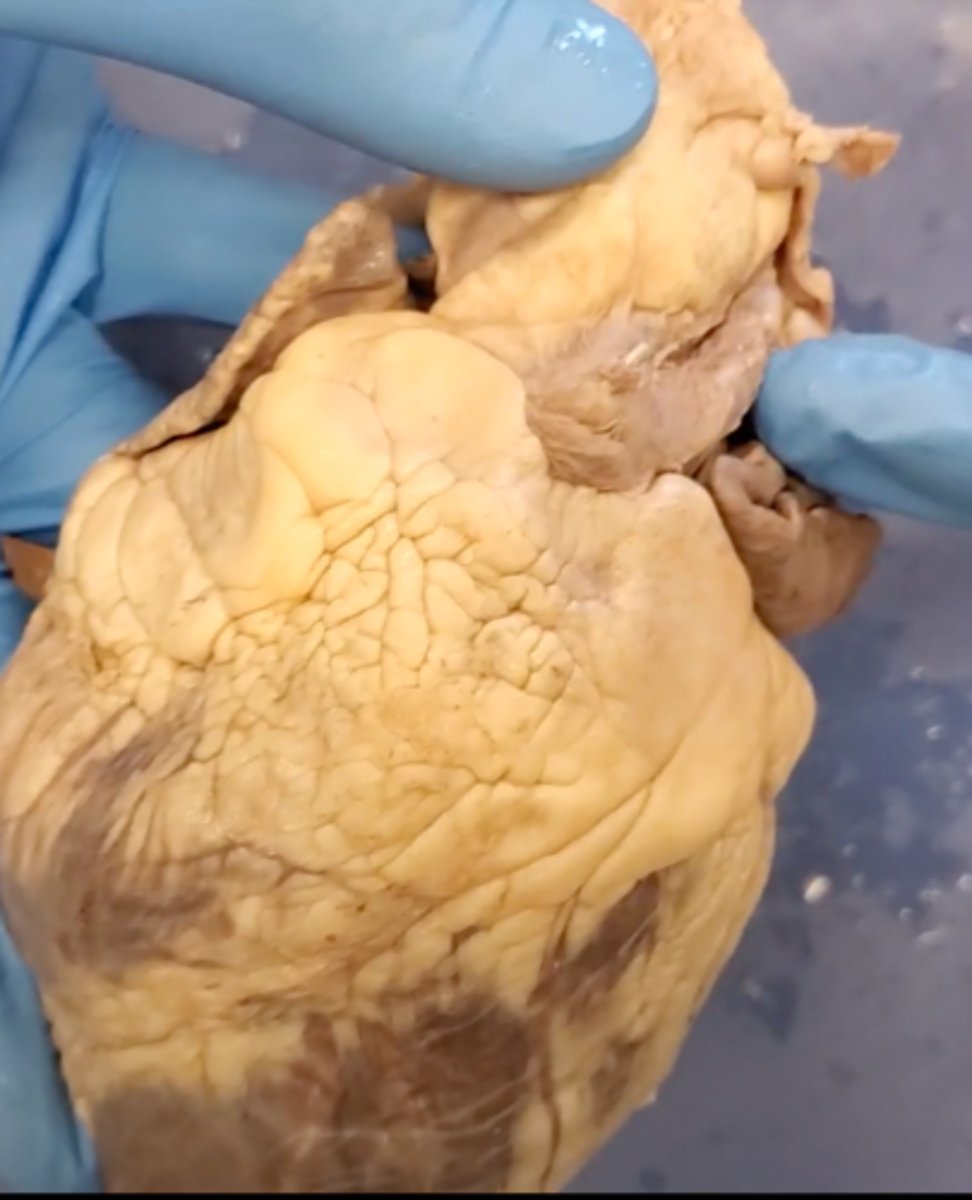

Tricuspid Valve (Right Atrioventricular Valve)

1-valve

Bicuspid valve (Left Atrioventricular Valve)

2-valve

Pulmonary Semilunar Valve

3-valve

Aortic Semilunar Valve

4-valve

Right Atrium

1-chamber

Left Atrium

2-chamber

Right Ventricle

3-chamber

Left Ventricle

4-chamber

Inferior Vena Cava

5-A vein that is the largest vein in the human body and returns blood to the right atrium of the heart from bodily parts below the diaphragm.

Superior Vena Cava

6-A vein that is the second largest vein in the human body and returns blood to the right atrium of the heart from the upper half of the body.

Aorta

7-The large arterial trunk that carries blood from the heart to be distributed by branch arteries through the body.

Pulmonary Trunk

8-carries blood from right ventricle to pulmonary arteries

Pulmonary veins

9-a vein carrying oxygenated blood from the lungs to the left atrium of the heart.

pulmonary trunk (model)

yellow sash of fat that tells you this if the front side of the heart (model)

t-shaped ribbon of fat on back side of heart (model)

Left ventricle (model)

has the most muscle mass because it has to pump blood to the whole body

apex (model)

base (model)

where everything connects

yellow sash of fat that tells you this if the front side of the heart (dissection)

pulmonary trunk (dissection)

t-shaped ribbon of fat on back side of heart (dissection)

left auricle (dissection)

right auricle (dissection)

left ventricle (dissection)

right ventricle (dissection)

right atrium (dissection)

left atrium (dissection)

bicuspid valve (dissection)

tricuspid valve (dissection)

aortic semilunar valve (dissection)

located between the left ventricle and the aorta

chordae tendineae (dissection)

thin bands of fibrous tissue that attach to the valves in the heart and prevent them from inverting